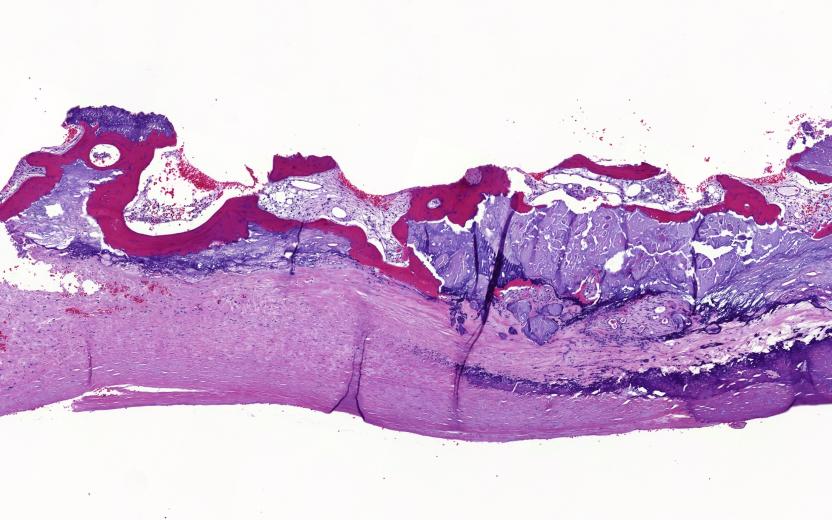

The Immunogenetics in Human Disease research group at the studies inflammation and complement genetics in complex human disease. The group has a strong translational approach, a wide network of clinical and research collaborators, and an understanding of the newest genetic and complement methodology.